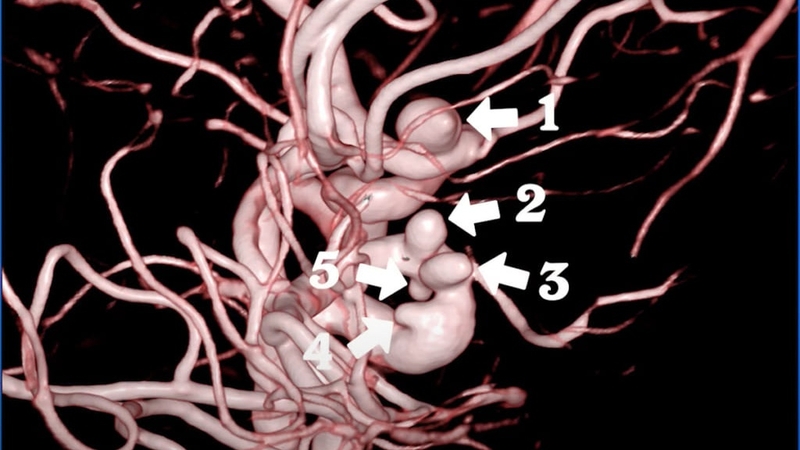

Chụp mạch máu số hóa xóa nền (DSA) cũng là một trong những cách được dùng rộng rãi hiện nay. Cách này sẽ sử dụng tia X để nghiên cứu máu trong cơ thể. Nó sẽ thấy rõ những phần đang bị tổn thương hoặc bệnh lý liên quan đến mạch máu trước khi đưa ra chỉ định can thiệp.

Chụp DSA chính là kỹ thuật kết hợp giữa chụp X quang với xử lý số dùng thuật toán xóa nền trên cách hình ảnh thu được trước và sau khi tiêm cản quang. Nó sẽ giúp hiện rõ hệ thống mạch máu trong cơ thể và máy tính sẽ tiến hành xóa mờ ảnh nền. Phương pháp này sẽ giúp phát hiện sớm các bất thường của dòng máu. Từ đó, bác sĩ có thể đưa ra phương pháp điều trị phù hợp cho bệnh nhân. Đặc biệt là ở khu vực thần kinh hoặc những vị trí khó phát hiện.